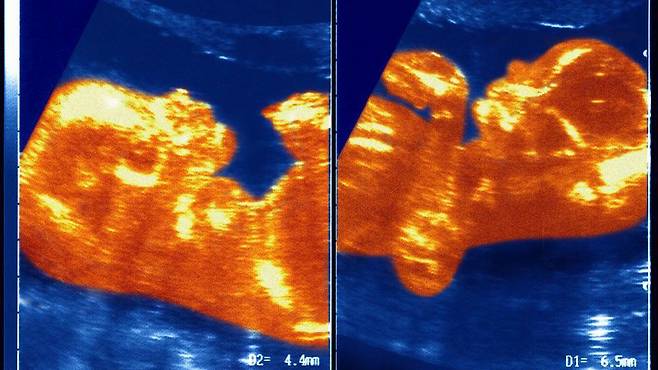

연구진은 태아 시절 마르틴스의 태반과 쌍둥이 남자형제의 태반이 접촉하면서 혈관이 연결되었고, 이로 인해 남아의 혈액이 여아에게 전달된 것으로 추정한다.

마시엘 교수는 "우리가 '쌍둥이 수혈 증후군'이라 부르는 혈액 이동이 발생한 것"이라면서 여아와 남아의 동맹과 정맥이 탯줄 안에서 얽히면서 남아는 자신의 혈액 성분을 여아에게 전달하게 되었다고 설명했다.